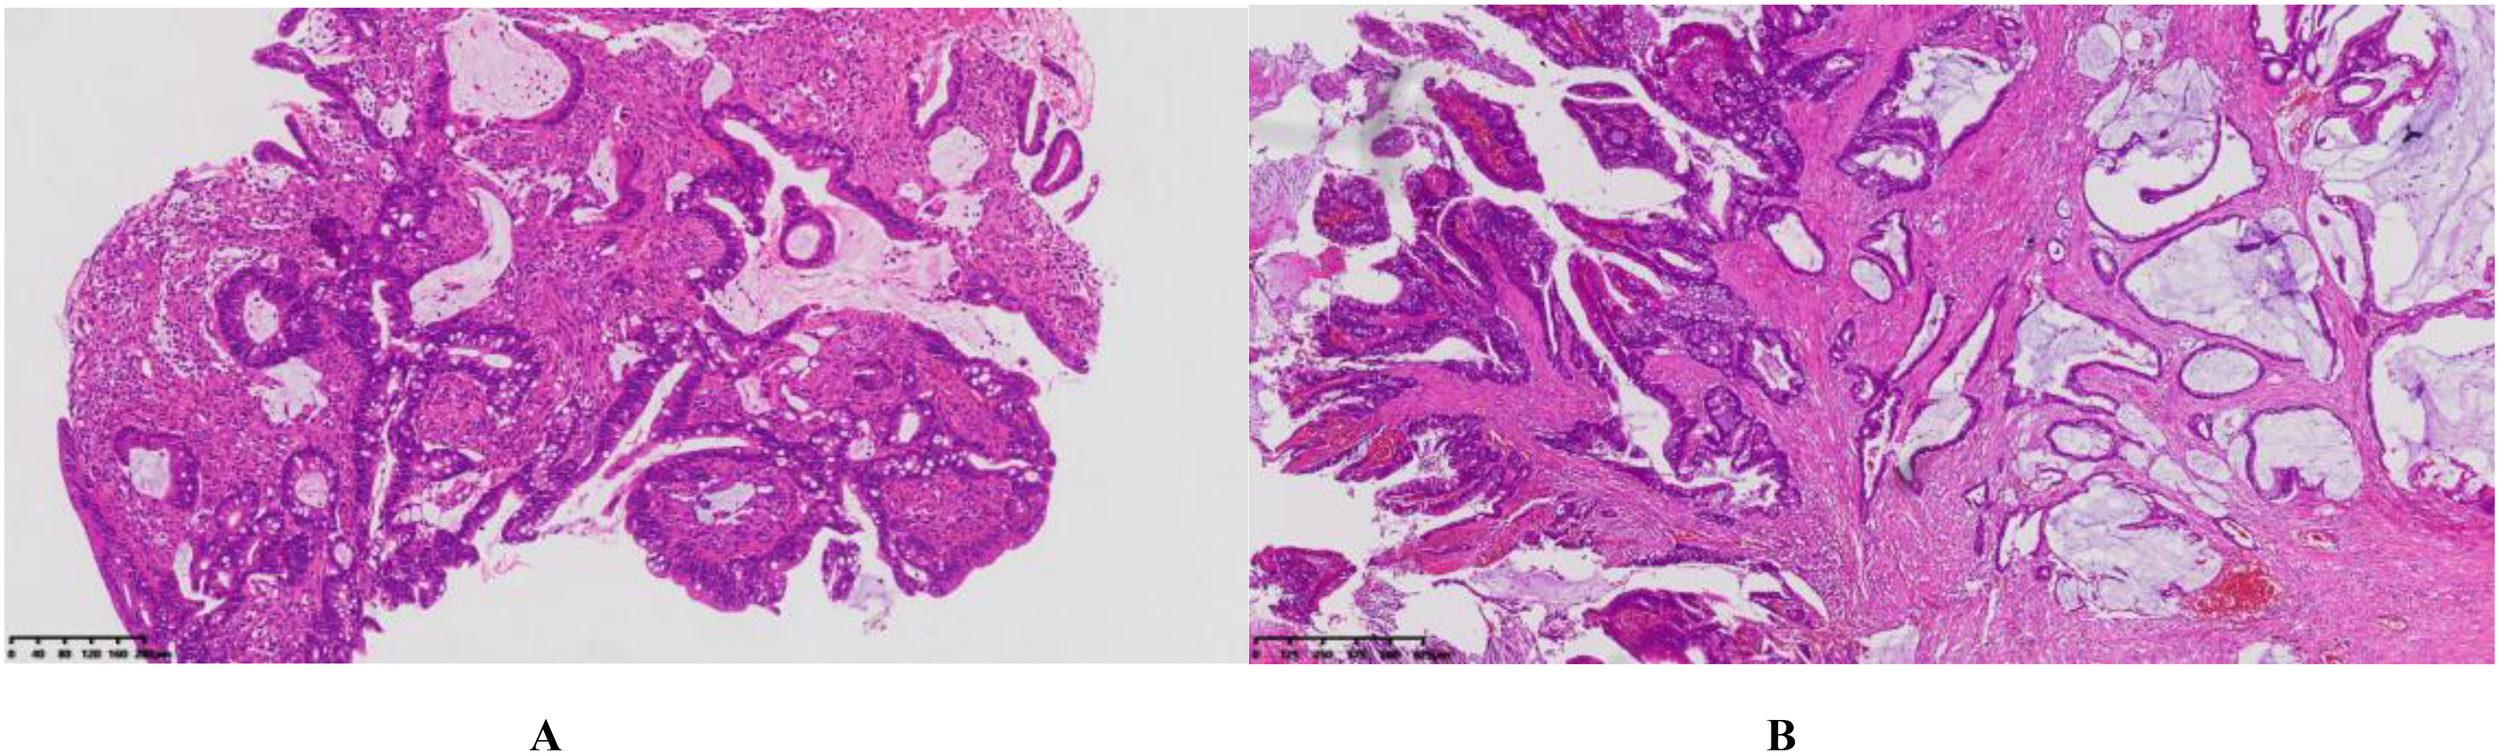

Figure 5

(A) Colonoscopy and histopathological examination (HE staining, ×10 magnification) (B) Postoperative pathological examination (HE staining, ×4 magnification): Moderately differentiated adenocarcinoma with partial mucinous adenocarcinoma. The tumor measures approximately 1.5 cm × 1 cm × 0.5 cm, infiltrates the deep muscular layer, and shows no clear evidence of vascular or perineural invasion.